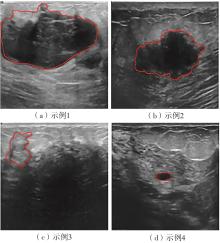

乳腺癌是全球女性最常见的恶性肿瘤之一,准确的病变分割对于乳腺癌的早期诊断与治疗具有重要意义。然而,由于病变形态的多样性以及超声成像机制的复杂性,现有基于深度学习的乳腺超声图像病变分割方法在分割准确性方面仍面临巨大挑战。为进一步提升乳腺超声图像中病变区域的分割精度,该文基于经典U-Net架构,提出了一种新型乳腺超声图像病变分割网络(CWSASKM-BBAM-Net)。首先,在网络中引入逐通道空间自适应选择核卷积模块(CWSASKM),根据不同通道的语义特征为每个空间位置自适应选择感受野大小,以增强多尺度信息的建模能力;然后,引入双向边界感知机制(BBAM),通过融合正向与反向注意力,对目标显著区域及其边界进行协同建模,同时逐步提升对非显著区域与病变区域的区分能力,以进一步强化边界信息的表达;最后,在3组公开乳腺超声图像数据集(BUSI、UDIAT和STU)上开展分割实验。结果表明:该方法在数据集BUSI上的杰卡德指数、精确率、召回率和Dice相似系数分别为71.97%、82.85%、81.40%和80.44%,较次优方法分别提升1.69、1.05、1.28和1.84个百分点;在数据集UDIAT上,这4项指标分别达到78.14%、88.31%、86.73%和86.10%,较次优方法分别提升了2.75、2.04、0.56和2.01个百分点;在外部数据集STU上,该方法也取得了优于其他方法的整体表现。实验结果表明,CWSASKM-BBAM-Net在乳腺超声图像分割任务中展现出更优的整体性能。